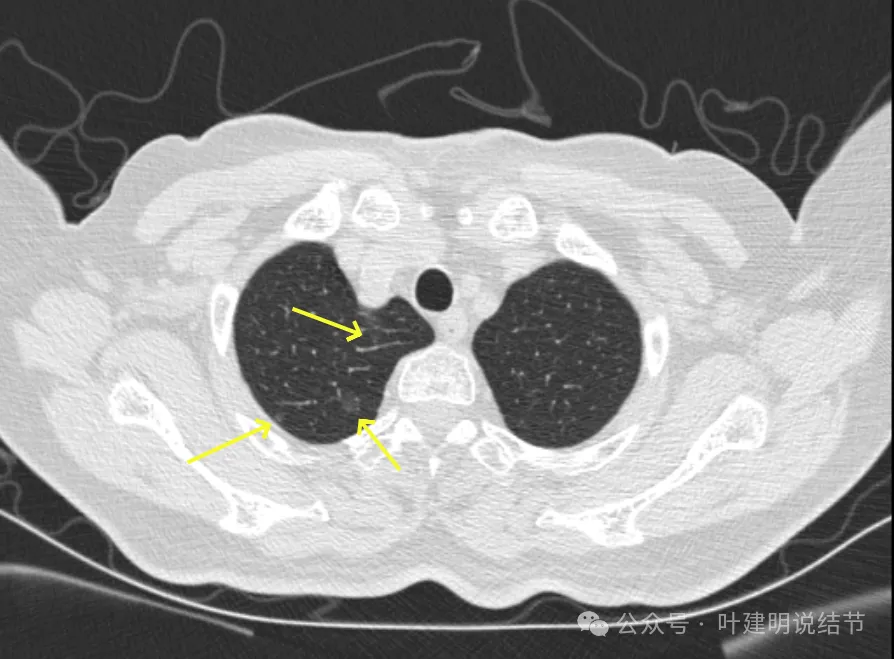

病灶15-18:右上叶淡磨玻璃结节,轮廓较清,有的界限稍不清。

病灶19-20:两肺淡磨玻璃结节,轮廓较清,小但边界清楚。